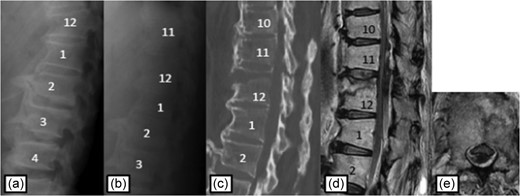

Case 1

Plain radiographs on initial assessment (a) and on admission (b); Sagittal CT image (c) showing the hyperextension fracture at T12; MRI T2-weighted image (d, e) showing the epidural hematoma compressing the dura matter.